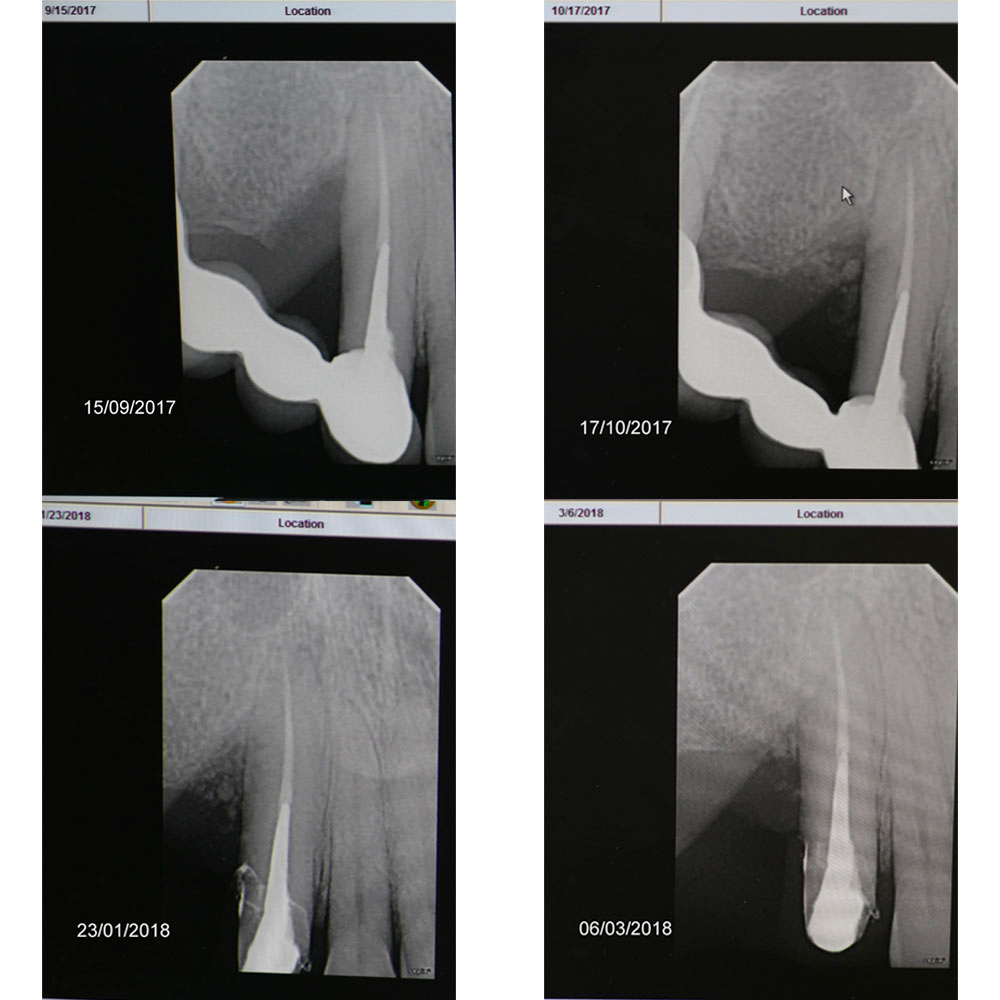

Rare documented case from 2017 to 2021 - bone regrowth after cleaning, curretage and applying DSI Syntoss Plus

Dear colleagues, I would like to share a clinical case that I have been observing since 2017. A patient came to the clinic with complaints of swelling and pain in the area 1.3, 1.4, 1.5. Conservative therapy was suggested, and after dealing with the acute period, a surgical procedure including cleaning of the periodontal pocket, scaling and root planing and filling the bone pocket with DSI Syntoss Plus that contains beta-tricalcium phosphate granules. The procedure was performed in 2017, the old bridge was replaced with a new one, which is fixed with temporary cement for regular revision due to the unstable condition of 2.6. The patient is unable to undergo implantation for a number of reasons, so the 2.6 will be kept until the last possible moment. Its mobility is grade 2 and the condition of the mucosa can be seen in the photo. The whole process of bone maturation is shown on the x-rays. Thank you for your attention.